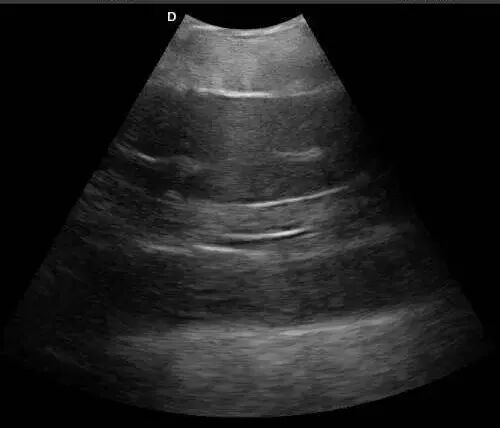

- Fish ultrasound examinations typically include roe assessment, milt assessment, swim bladder checks, and gonad evaluation. In this case, a portable laptop animal ultrasound machine

L3 was used at a sturgeon farm in Hubei to assess gonads and roe. A micro-convex probe was selected for the large sturgeon; for smaller individuals, a linear probe can be used.